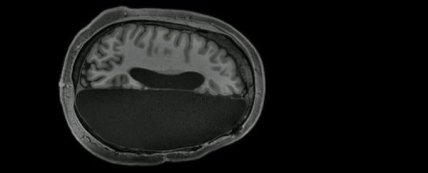

Ученые сделали снимки МРТ нескольких людей, живущих с половиной мозга. Работа позволила объяснить это явление.

Ответить на этот вопрос решили ученые из Калифорнийского технологического института. Они провели магнитно-резонансную томографию шестерым пациентам, которым в детстве было удалено полушарие мозга или крупная его часть из-за редкой и страшной формы эпилепсии. Эта процедура называется гемисферэктомией и используется только в том случае, когда приступы эпилепсии угрожают жизни пациента или специальные препараты не подействовали.

Сравнивая МРТ-снимки этих участников с шестью контрольными, у которых не было удалено ни одной части мозга, а также с базой данных из 1482 изображений, авторы работы обнаружили, что паттерн активности мозга в состоянии покоя у участников с половиной мозга удивительно похож на наблюдаемый у людей, имеющих весь объем мозгового вещества. Но команда также выявила разницу: у участников, которым была сделана гемисферэктомия, было найдено гораздо больше связей между мозговыми сетями.

Это увеличение числа связей было обнаружено у всех шести пациентов, прошедших через гемисферэктомию. Но во всех случаях образование связей наблюдалось между различными сетями. Так, например, сеть внимания показала больше подключений к визуальной сети, чем обычно. Это увеличение связей между сетями отражает то, как оставшаяся часть мозга компенсирует потерю его «вычислительных» ресурсов, чтобы поддерживать когнитивные функции и сознание, объясняют исследователи.